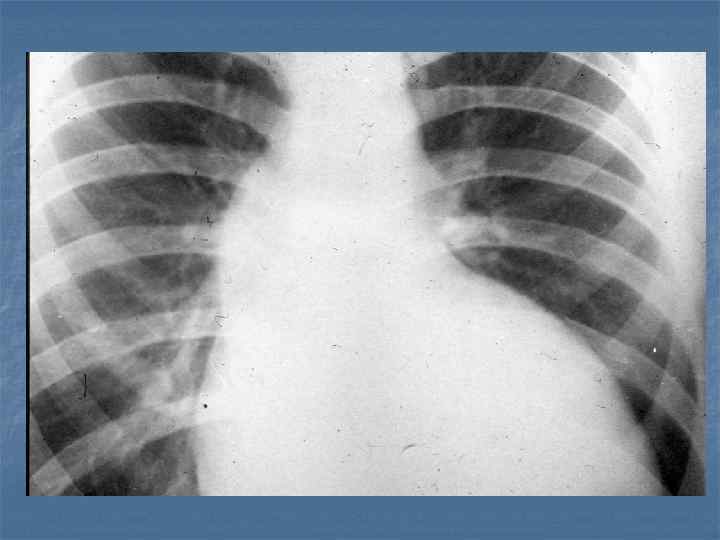

Рентгенограмма грудной клетки больного со стенозом трехстворчатого клапана во второй косой проекции.

Рентгенограмма грудной клетки больного с недостаточностью трехстворчатого клапана во второй косой проекции.